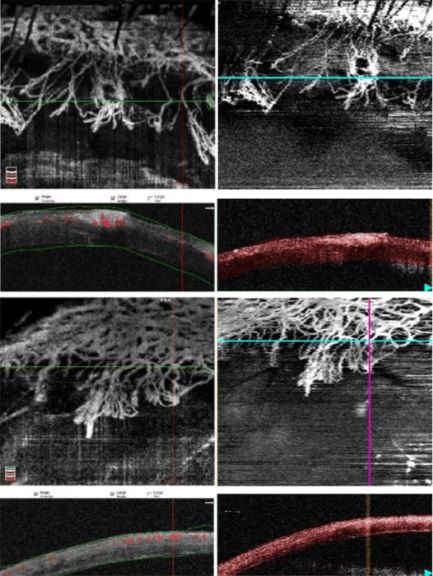

使用数字裂隙灯相机在标准漫射照明下捕获彩色SLP图像。图1在第1周和第2周在相同感兴趣区域的时间点期间拍摄的具有代表性的OCTA图像。从两个系统的每个OCTA中提取在角膜B扫描每50μm处分割的相同代表性图像,并进行比较,如图2所示。SSADA系统中的分割算法是基于黄斑B扫描层分割的,而OMAG OCTA分割是基于为研究目的而开发的自定义并行层分割的。

在(a)第2周和(b)第1周随访成像时拍摄的OCTA扫描的代表性示例。在第2周的时间点(图1a)和第1周的时间点(图1b)拍摄的OCTA图像示例,用全角膜横截面分割比较SSADA OCTA(左)和OMAG OCTA系统(右)。与OMAG OCTA相比,SSADA OCTA具有更高的图像质量性能。SSADA B扫描中突出显示的红色区域表示与正面图像中水平绿色线标记的横截面相对应的血流量。 确认角膜血管存在于基质层深处。

正面OCTA分割图像的比较。图示了对于图1a中在第2周随访时间点成像的OCTA图像,在SSADA OCTA系统中每50μm深度处对OMAG OCTA系统执行的正面和相应的横截面分割。图1b在第1周的随访时间点的类似分割图如图2c所示,使用SSADA OCTA,图2d使用OMAG OCTA。SSADA横截面B扫描中的分割线标记为绿色,而OMAG B扫描中的分割线则标记为红色。 如图2a和c所示,从表层投射的SSADA OCTA在较深层分割的正面图像中存在血管。